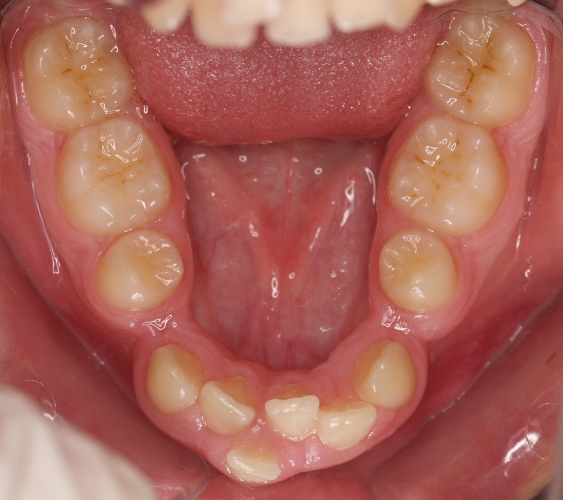

La paciente O.O. acude a nuestra consulta por:

– Canino 13 e incisivo lateral 42 en posición ectópica.

– Canino 23 incluido.

Con lo que decide realizarse un tratamiento de ortodoncia de duración de 24 meses con brackets damon Q.

CASO COMPLETO: